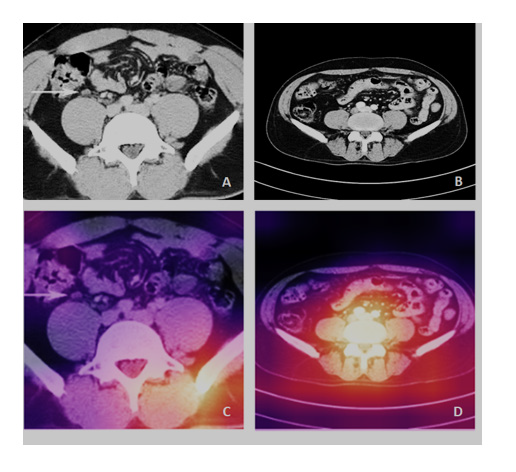

Moreover, the confusion matrix of Figure 4 shows that the ResNet-34 had a success rate of 99.57 and 100% for classifying all source CT images of Abdominal Lymphadenopathy patients and Healthy Controls, respectively. The overall accuracy of the Res- Net-34 for testing the subset of random CT images was as high as 99.79%, which means an error rate as low as 0.21%. Figures 5A and 5B show samples of input CT grayscale images batch for Abdominal Lymphadenopathy patients and Healthy Controls. Figures 5C and 5D also show samples of the colored activation map of the ResNet-34 final output layer for the two different subsets. The activation map is a proper visual diagnostic representation, highlighting specific lymph node lesions of a CT image, contributing to the added effect of the ResNet-34 classification process.

The added effect due to the success rate of the ResNet-34 was 99.57% and 100% for classifying all source CT images of Abdominal Lymphadenopathy and Healthy Controls, respectively (Figure 4). The overall accuracy of the ResNet-34 for testing the subset of random CT images used for the detection and classification of lymph node lesions was as high as 99.79%, with a very low error rate of 0.21% in the testing phase compared to the 3.6% showed for the benchmarked ResNet-34 [12]. We have recently shown similar results using the same ResNet-34 model, which showed high performance and precision in detecting and classifying COVID-19, pneumonia, and the Normal Controls from CXR images with an accuracy of 100%, 99.6%, and 98.9, with overall accuracy of 99.5% for the testing subset for diagnosis [10]. We employed the Grad- CAM method to localize and visualize an ROI within CT images, consistently highlighting a specific area common in shape, pattern, or location among CT images within the same class but distinct from images in other modality classes [14]. The activation map (Figures 5C and 5D) is thus an informative visual diagnostic representation, highlighting certain morphological anomalies of lymph nodes in a CT image, contributing the most to the ResNet-34 classification process.